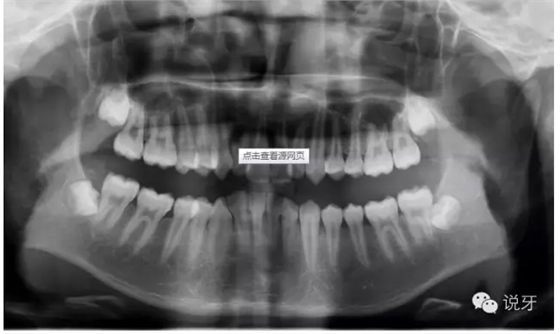

2、拍片

拍X光牙齒及頭部骨頭照片。目的是為了看清牙齒及骨骼發(fā)展方向,以利于之后制定準(zhǔn)確的矯正方法。